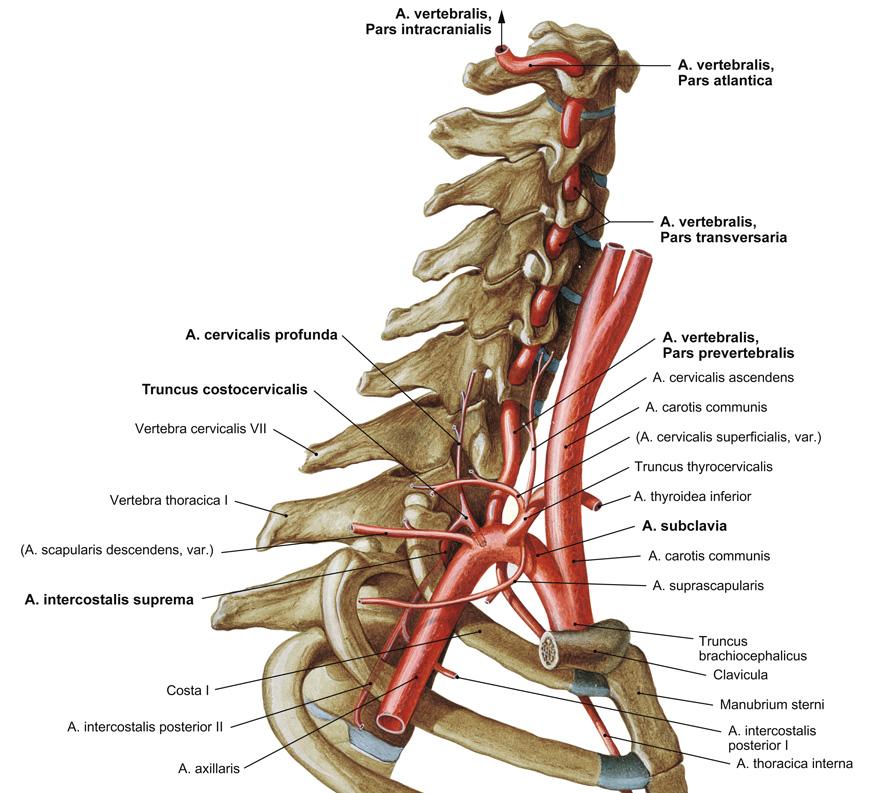

Fig 3.13: a. subclavia

|

|

Fig 3.14: a. subclavia - zijtakken

glandula thyroidea = schildklier (groen) rib I tuberculum m. scalenus anterior v subclavia dextra -

truncus brachiocephalicus

a carotis communis (ACC) -

a subclavia dextra

a vertebralis (naar foramen transversarium C6-C2, a. basilaris) -

truncus thyrocervicalis

a thoracica interna = a. mammaria (langs sternum) -

truncus costocervicalis (posterieur)

|

Fig 3.15: a. vertebralis

A C3-C6

proc. transversus foramen transversarium

B C1-C2

|

|